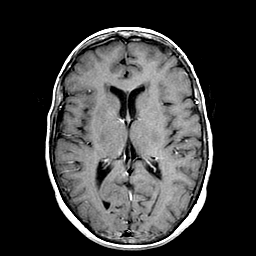

Metastatic Adenocarcinoma of the Colon: T1-weighted MR -- Slice #13

[Home][Help][Clinical] Slice 13